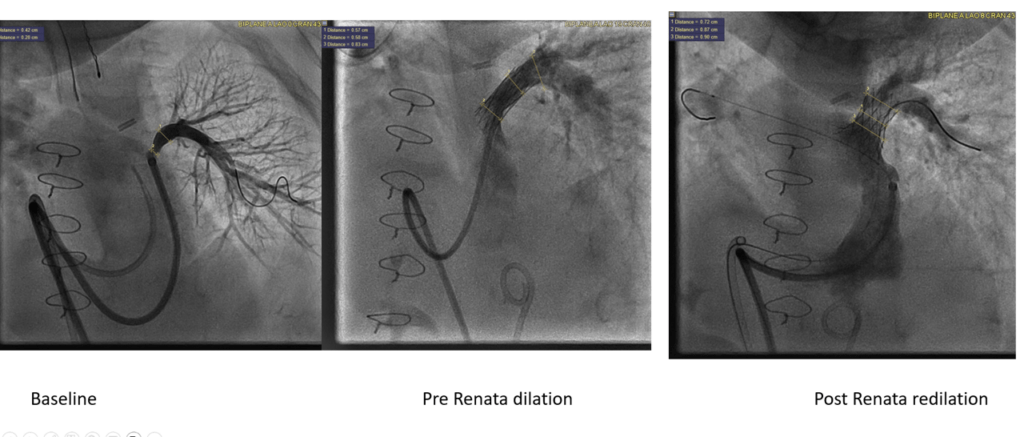

Novel Heart Stent for Kids Draws Praise

Shabana Shahanavaz, MD, MBBS12/4/2024